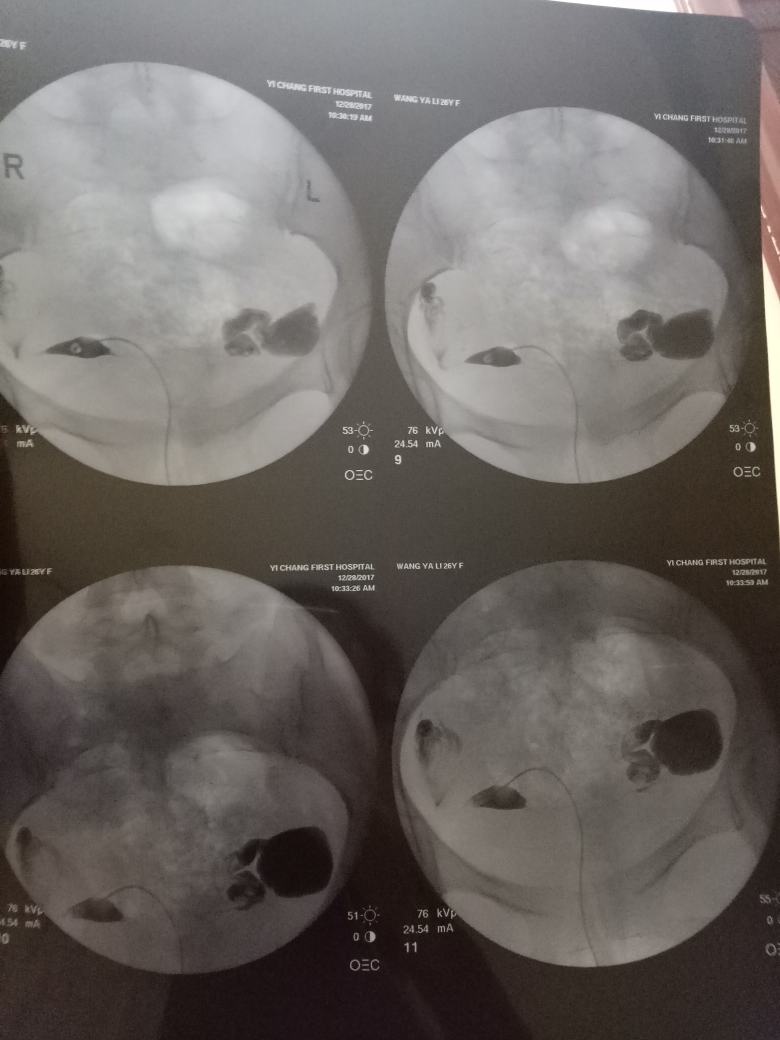

在現(xiàn)代醫(yī)學(xué)中,造影技術(shù)廣泛應(yīng)用于臨床診斷,對(duì)于不孕癥的診斷和治療也起到了重要作用,造影是一種通過(guò)放射線、超聲波等影像技術(shù)觀察人體內(nèi)部結(jié)構(gòu)和狀況的方法,完成造影后的第二個(gè)月,很多夫婦關(guān)心是否容易懷孕,造影本身并不會(huì)直接影響懷孕,但了解身體情況后,有針對(duì)性地進(jìn)行治療和調(diào)理,確實(shí)有助于提高懷孕的幾率。

通過(guò)造影技術(shù),醫(yī)生可以清晰地觀察到子宮內(nèi)部環(huán)境,如子宮內(nèi)膜厚度、輸卵管通暢情況等,若子宮環(huán)境良好,第二個(gè)月懷孕的機(jī)會(huì)將大大增加。